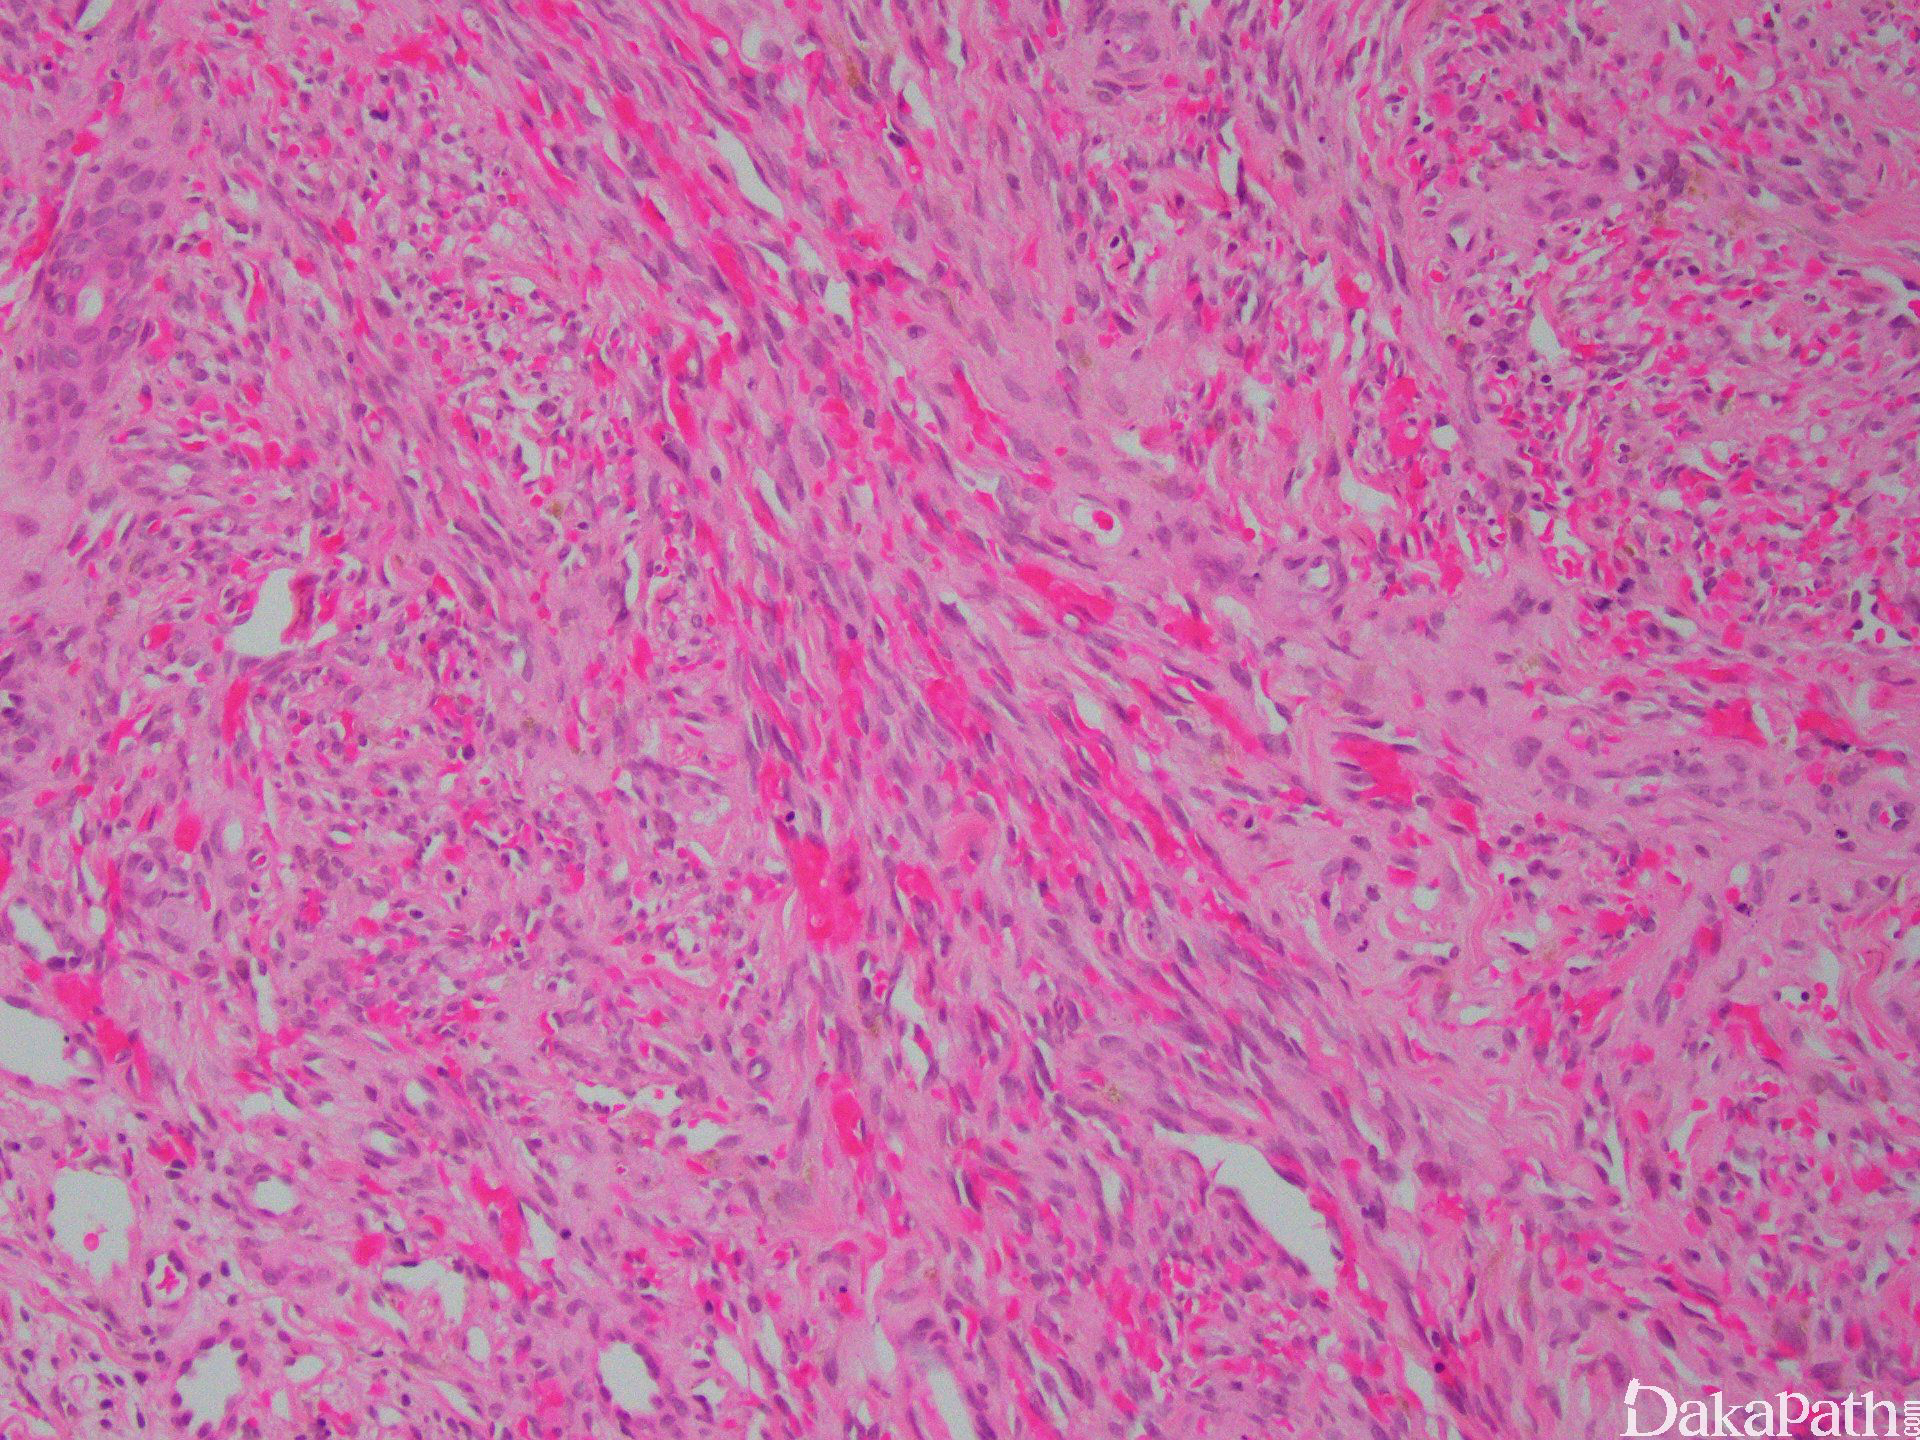

IV 期为结节期:结节期的病变边界清楚,主要由网状或裂隙状的毛细血管及其周围纵横交错的嗜酸性梭形细胞组成,梭形细胞有一定异型性,核分裂偶见;梭形细胞和血管之间为含有红细胞的裂隙,横切面呈筛孔状或蜂窝状,在梭形细胞内或细胞外可见抗淀粉酶消化 PAS 阳性的嗜伊红色透明小体,结节的边缘常见炎症细胞浸润、含铁血黄素沉着和扩张的血管。 典型的卡波西肉瘤细胞无明显的异型性,核分裂像也不多见,但少数病例中瘤细胞分化较差,异型性明显,可见较多的核分裂像。